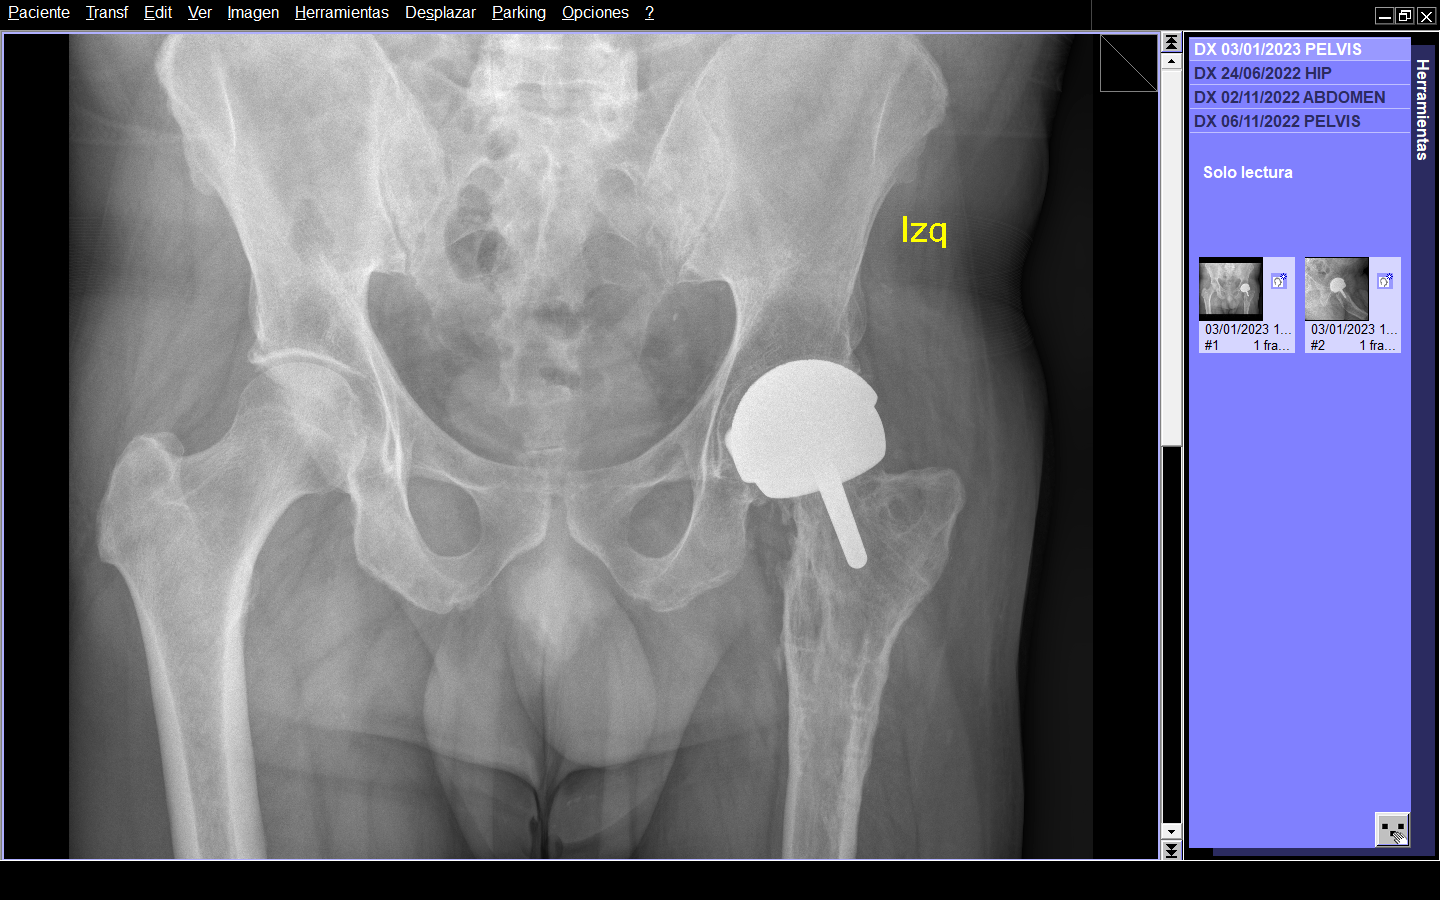

Figura 3. Radiografía AP de ambas caderas postoperatoria.

Por abordaje posterior de Moore, se llevó a cabo apertura longitudinal de la fascia lata y tenotomía del tendón conjunto de rotadores. Debido a la necesidad imperiosa de exposición femoral, la inserción de la expansión del glúteo mayor se libera de la línea áspera. Se realizó artrotomía en “T” invertida con luxación de cadera izquierda. Siguiendo la técnica descrita, se introduce clavo guía en cabeza femoral y se realiza preparación de la cabeza y cuello femoral para componente femoral 50. Se realizaron orificios para mayor penetración de cemento. Una vez terminada la preparación femoral, se fresa el cotilo hasta un diámetro de 56mm como lo marca la técnica. A manera de press-fit se coloca el componente acetabular definitivo. Se procede a cementar el componente femoral en su sitio y se reduce la articulación. Se prueba la estabilidad, la cual fue satisfactoria y se procede a cerrar por planos realizando reinserción de rotadores y cápsula en trocánter mayor. (Figura 3 y 4) La duración del procedimiento quirúrgico fue de 36 minutos y un sangrado de 150 cc.